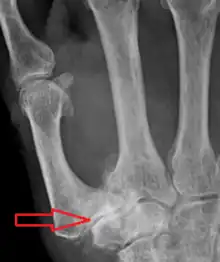

| Osteoarthritis of the trapeziometacarpal joint | |

Trapeziometacarpal osteoarthritis (TMC OA) is, also known as osteoarthritis at the base of the thumb, thumb carpometacarpal osteoarthritis, basilar (or basal) joint arthritis, or as rhizarthrosis.[3][1][2] This joint is formed by the trapezium bone of the wrist and the metacarpal bone of the thumb. This is one of the joints where most humans develop osteoarthritis with age.[4] Osteoarthritis is age-related loss of the smooth surface of the bone where it moves against another bone (cartilage of the joint).[3][5] In reaction to the loss of cartilage, the bones thicken at the joint surface, resulting in subchondral sclerosis. Also, bony outgrowths, called osteophytes (also known as “bone spurs”), are formed at the joint margins.[6]

TMC OA is diagnosed based on symptoms and signs.[8] Radiographs can confirm the diagnosis and the severity of TMC OA. Other diagnoses in this region include scaphotrapezial trapezoid arthritis and first dorsal compartment tendinopathy (De Quervain syndrome) although these are usually easy to distinguish.